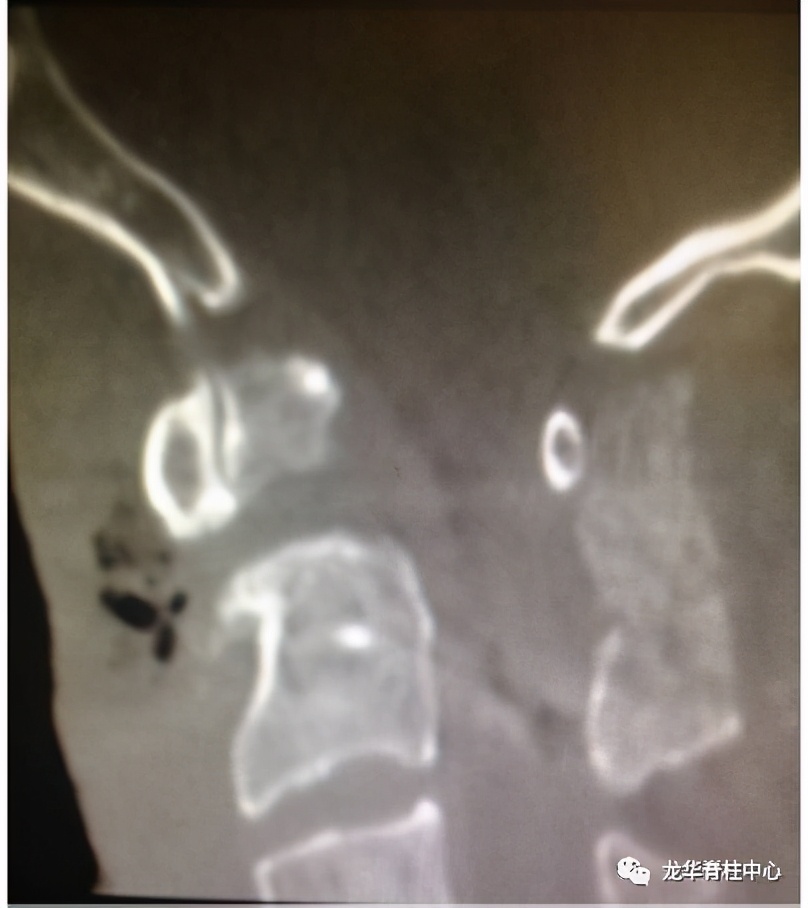

显微镜下寰枢椎脱位经口松解、后路固定术

开展深圳市首例寰枢椎脱位经口咽松解、后路椎弓根钉板内固定术